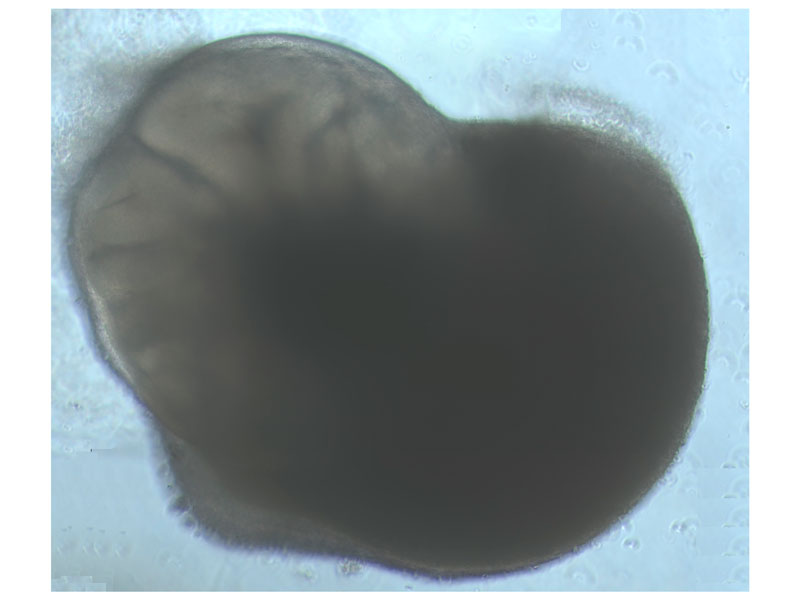

"SARS-CoV-2 is a virus that is transmitted through the air, because of this, it has been necessary to adapt the high-level biosecurity level facilities for this factor and offer adequate training to all the research staff who come to work on these projects. Now, not only can we study how the real infection develops, but we are also preparing to work on other similar viruses," explains the Director of the CMCiB and the Chairman of the Biosecurity Committee, Dr Pere-Joan Cardona. "Having these resources on the Can Ruti Campus means we can tackle much more ambitious projects in the area of infectious diseases. The fact that we are carrying out a project on organoids also means that the results are as similar as possible to the equivalent in humans, and this is vital," adds ICREA Research Professor at IrsiCaixa Dr Javier Martínez-Picado. Organoids, which have already been used previously in research, are mini-organs of a few millimetres in diameter. These are usually created from stem cells and have the potential to form any human organ. In this case, they will form mini lungs and brains.

In line with the concept of 3R, organoids permit research to advance by using them as alternative models to meet different biomedical challenges. They can replace animal models, which would have been used to develop the studies. The project, which was initiated by researchers of IrsiCaixa and the IBE is based on generating mini-lungs and mini-brains in the laboratory, produced from stem cells. Healthy mini-organs will be infected with SARS-CoV-2 and the level of deterioration will be evaluated. Previously, they will have been treated with drugs that are potentially effective against the virus, so they can be followed up to see which drugs prevent the virus from replicating.

"We will analyze the effect of the infection on humans using molecular techniques. Additionally, we will use microscopic photographs of the organoids in each phase of the infection to monitor the evolution of the infection using an artificial intelligence algorithm, designed in collaboration with Dr Lao of the CNAG-CRG (Centre Nacional d'Anàlisi Genòmica - Centre de Regulacio Genòmica). This system will recognize patterns of infection and we will be able to rapidly evaluate which drugs are working better," explains Dr Sandra Acosta, the researcher in charge of the project at the Institute of Evolutionary Biology (IBE).